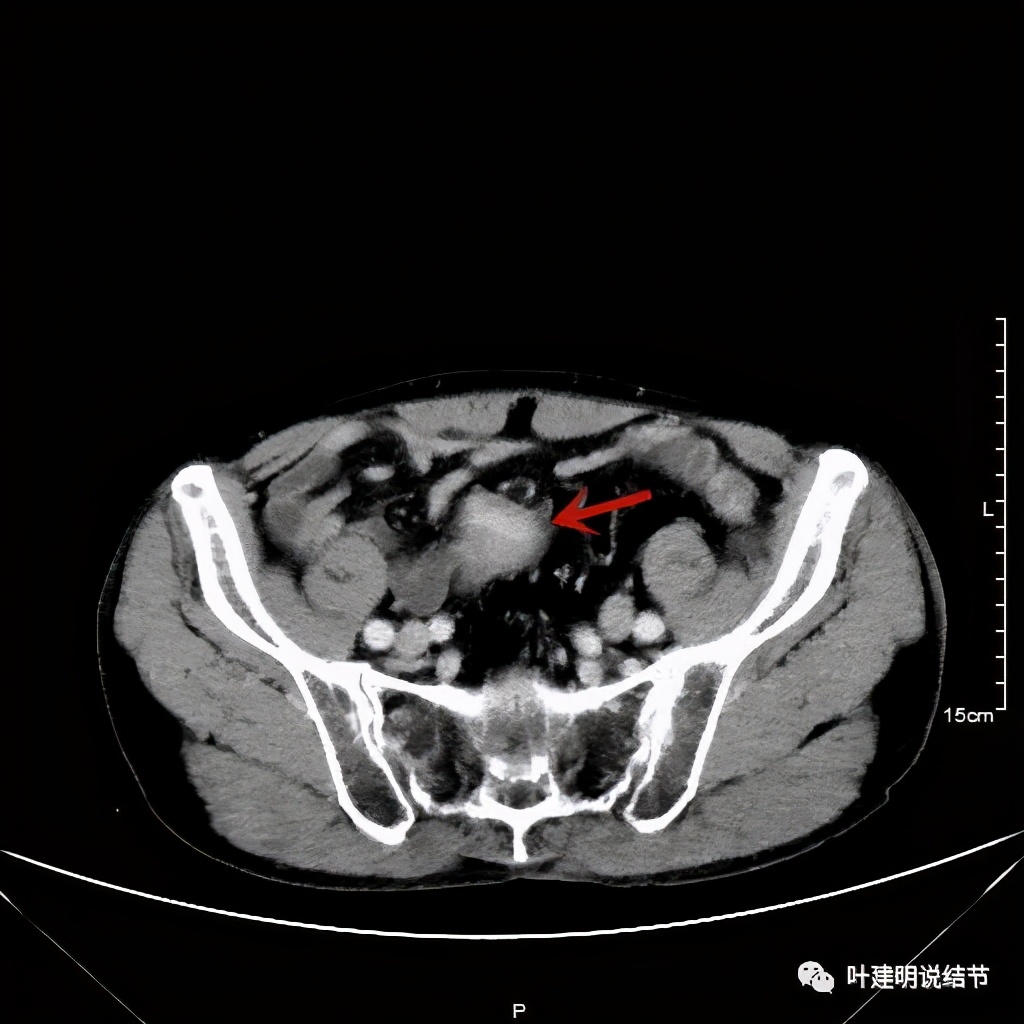

肠镜所示乙结肠肿瘤大一些,有5厘米,镜下也见占位明显,表面不平

活检后食管是鳞癌,结肠是腺癌。下面是其术前CT的图像:

以上诸图红色示乙状结肠肿瘤,绿色示其下方正常的乙状结肠及直肠